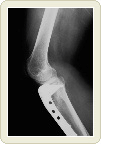

손발의 뼈는 어떻게 되나요?

손발의 단면을 보면 마치 꼬치모양인데 고리 안쪽이 골수이다. 우리는 가끔「뼈를 깎는 듯한 고생」이라는 말을 한다. 연필을 깎듯이 외부부터 가늘게 깎이는게 아니라 안쪽 골수부분부터 감소하기 시작한다. 지속적으로 감소하면「구멍」이 생긴 것과 같은 상태가 되면서 약해진다. 그래서 넘어지면 골절을 입게 된다.

그 밖에 대퇴골부분의 골절도 자주 발생한다.

노인이 옆으로 넘어지면 발목을 부딪치고 뼈가 부러져 와병생활의 원인이 되기도 한다.

최근 대퇴골경부골절이 많이 발생하고 있다. 참고로 일본은 1980년에 25,000명 정도이던 환자가 1987년에 53,000명, 지금은 72,000명~75,000명 정도의 환자가 발생하고 있다고 한다.